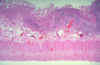

Pseudomembranous Colitis

Pseudomembranous Colitis

Pseudomembranous Colitis

Pseudomembranous Colitis

Pseudomembranous Colitis